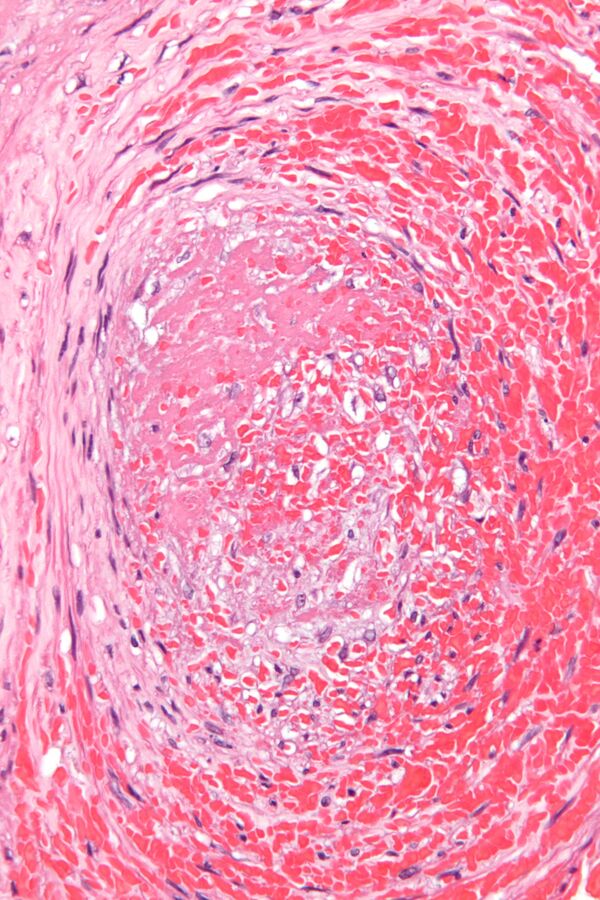

- Смешанные тромбы встречаются чаще всего. Они имеют слоистое строение — слоистый тромб — и пестрый вид, содержат элементы как белого, так и красного тромба. В смешанном тромбе различают головку (имеет строение белого тромба), тело (собственно смешанный тромб) и хвост (имеет строение красного тромба). Головка прикреплена к эндотелиальной выстилке сосуда, что отличает тромб от посмертного сгустка крови. Слоистые тромбы образуются чаще в венах, в полости аневризмы аорты и сердца.